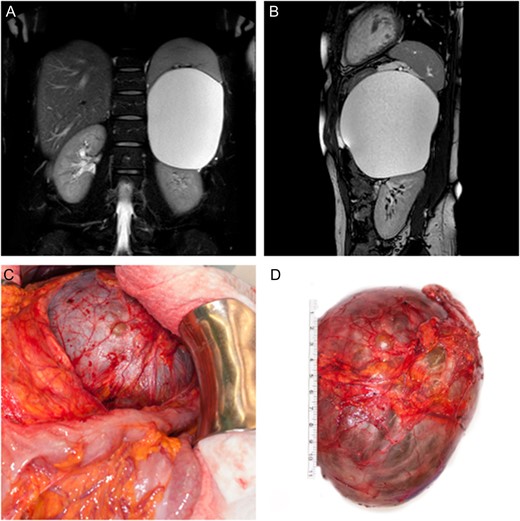

We performed an upper midline laparotomy. To ensure a good anatomical overview, mobilization of the left colonic flexure was necessary and the omental bursa was entered. The distal part of the pancreas showed close proximity to the cystic lesion and needed careful separation. After adhesiolysis between the splenic surface, the posterior gastric wall as well as the parietal peritoneum, the left adrenal gland with its associated vein, was found to be the origin of the cystic tumor. Hence total adrenalectomy was performed in order to remove the intact cystic lesion (Fig. 1C and D). Following a short period of postoperative nausea and vomiting, gradual return to a normal diet was possible. The patient was discharged on the sixth postoperative day.

(A, B) Coronal and sagittal T2 weighted, fat suppressed MR image of the abdomen showing displacement of the spleen as well as the left kidney by the adrenal tumor. (C) Intra-operative finding showing close proximity of the cystic lesion to the left colonic flexure. (D) Surgically excised cystic tumor together with the left adrenal gland.